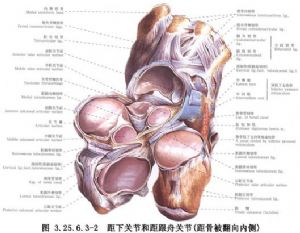

三关节融合术是将跟距、跟骰和距舟三个关节面及部分骨质切除,使其骨性融成为一体,用以矫正足部畸形,恢复足的正常位置,增加稳定性。手术相关解剖见下图(图3.25.6.3-1,3.25.6.3-2)。

局部解剖示意图见12.27.1.6-1。